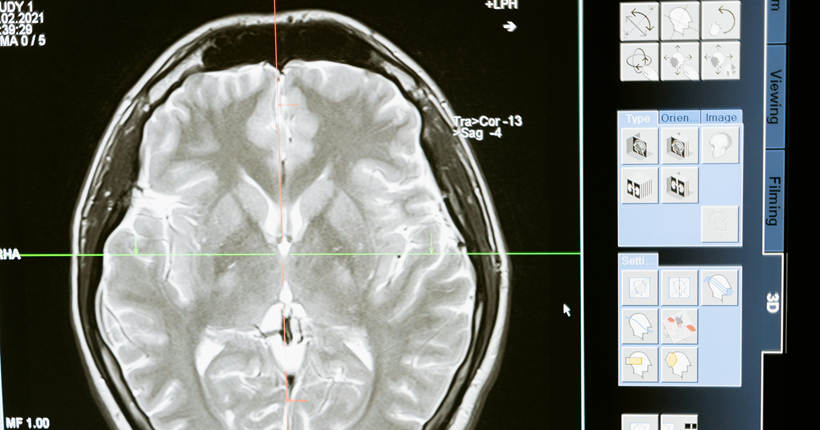

Factores de riesgo y biomarcadores de la enfermedad de Alzheimer

La enfermedad de Alzheimer, constituye un problema sanitario y social de gran magnitud; precisa de diagnóstico y terapéutica precoces. Dispersos estudios de diversa metodología se refieren a la predicción de la demencia a partir de factores de riesgo. No obstante, existen insuficientes investigaciones que analicen en conjunto factores de riesgo y biomarcadores y los asocien; lo que ha limitado la posibilidad de acciones preventivas y terapéuticas precoces en pacientes en riesgo.

Se realizó una revisión sistemática de la literatura con el objetivo de analizar los factores de riesgo y los biomarcadores de la enfermedad de Alzheimer. Se realizó una búsqueda de los términos: "demencia/ dementia", "enfermedad de Alzheimer/ Alzheimer’s disease" "factor de riesgo/ risk factor", "biomarcador/ biomarker", en las bases de datos: PubMed/Medline, Scopus, Scielo, Lilacs y mediante el buscador Google académico; se consultaron documentos no publicados. Se clasificaron los resultados de la búsqueda mediante el examen del título y resumen.

De 154 investigaciones encontradas se incluyeron revisiones, metaanálisis, estudios observacionales y ensayos publicados desde el año 2017 hasta el 2023, en idioma español, inglés y portugués. Se excluyeron trabajos duplicados, libros o capítulos de libros, estudios cualitativos, que no se relacionaran con el tema o sin acceso al texto completo. Tras la aplicación de los criterios, se obtuvieron 32 estudios observacionales, 23 revisiones, 12 metaanálisis, y 3 ensayos. Se revisaron los documentos completos para verificar el cumplimiento de los criterios de inclusión.

Los principales factores de riesgo encontrados son edad avanzada, menor educación, poca actividad física, hábito de fumar, consumo excesivo de alcohol, hipertensión arterial, diabetes, obesidad, depresión, pérdida o disminución de la audición, aislamiento social, los traumas craneales y la contaminación ambiental. Los biomarcadores fundamentales son: los marcadores que se utilizan en los estudios de neuroimágenes como la tomografía por emisión de positrones (PET) Amiloide, PET tau, PET con fluorodesoxiglucosa (FDG); y en líquido cefaloraquídeo y plasma: Aβ42, Aβ42/Aβ40, p tau 217, p tau 181, proteína gliofibrilar ácida (GFAP), y neurofilamentos de cadena ligeras. Se reconoció el uso de los parámetros cuantificados en el P300 como biomarcadores complementarios clasificadores de la presencia y del nivel de disfunción cognitiva de etiología enfermedad de Alzheimer posible.

La mayoría de los estudios analizados, aunque abordan con profundidad la relación de los factores de riesgo y la enfermedad de Alzheimer, tienen limitaciones al asociar unos factores con otros, o con biomarcadores. Se requieren estudios longitudinales, a partir de la presencia de los factores de riesgo asociados a biomarcador, desde edades pregeriátricas en pacientes sanos, que tengan como salidas el deterioro cognitivo y el desarrollo de la demencia, para construir un modelo de predicción.